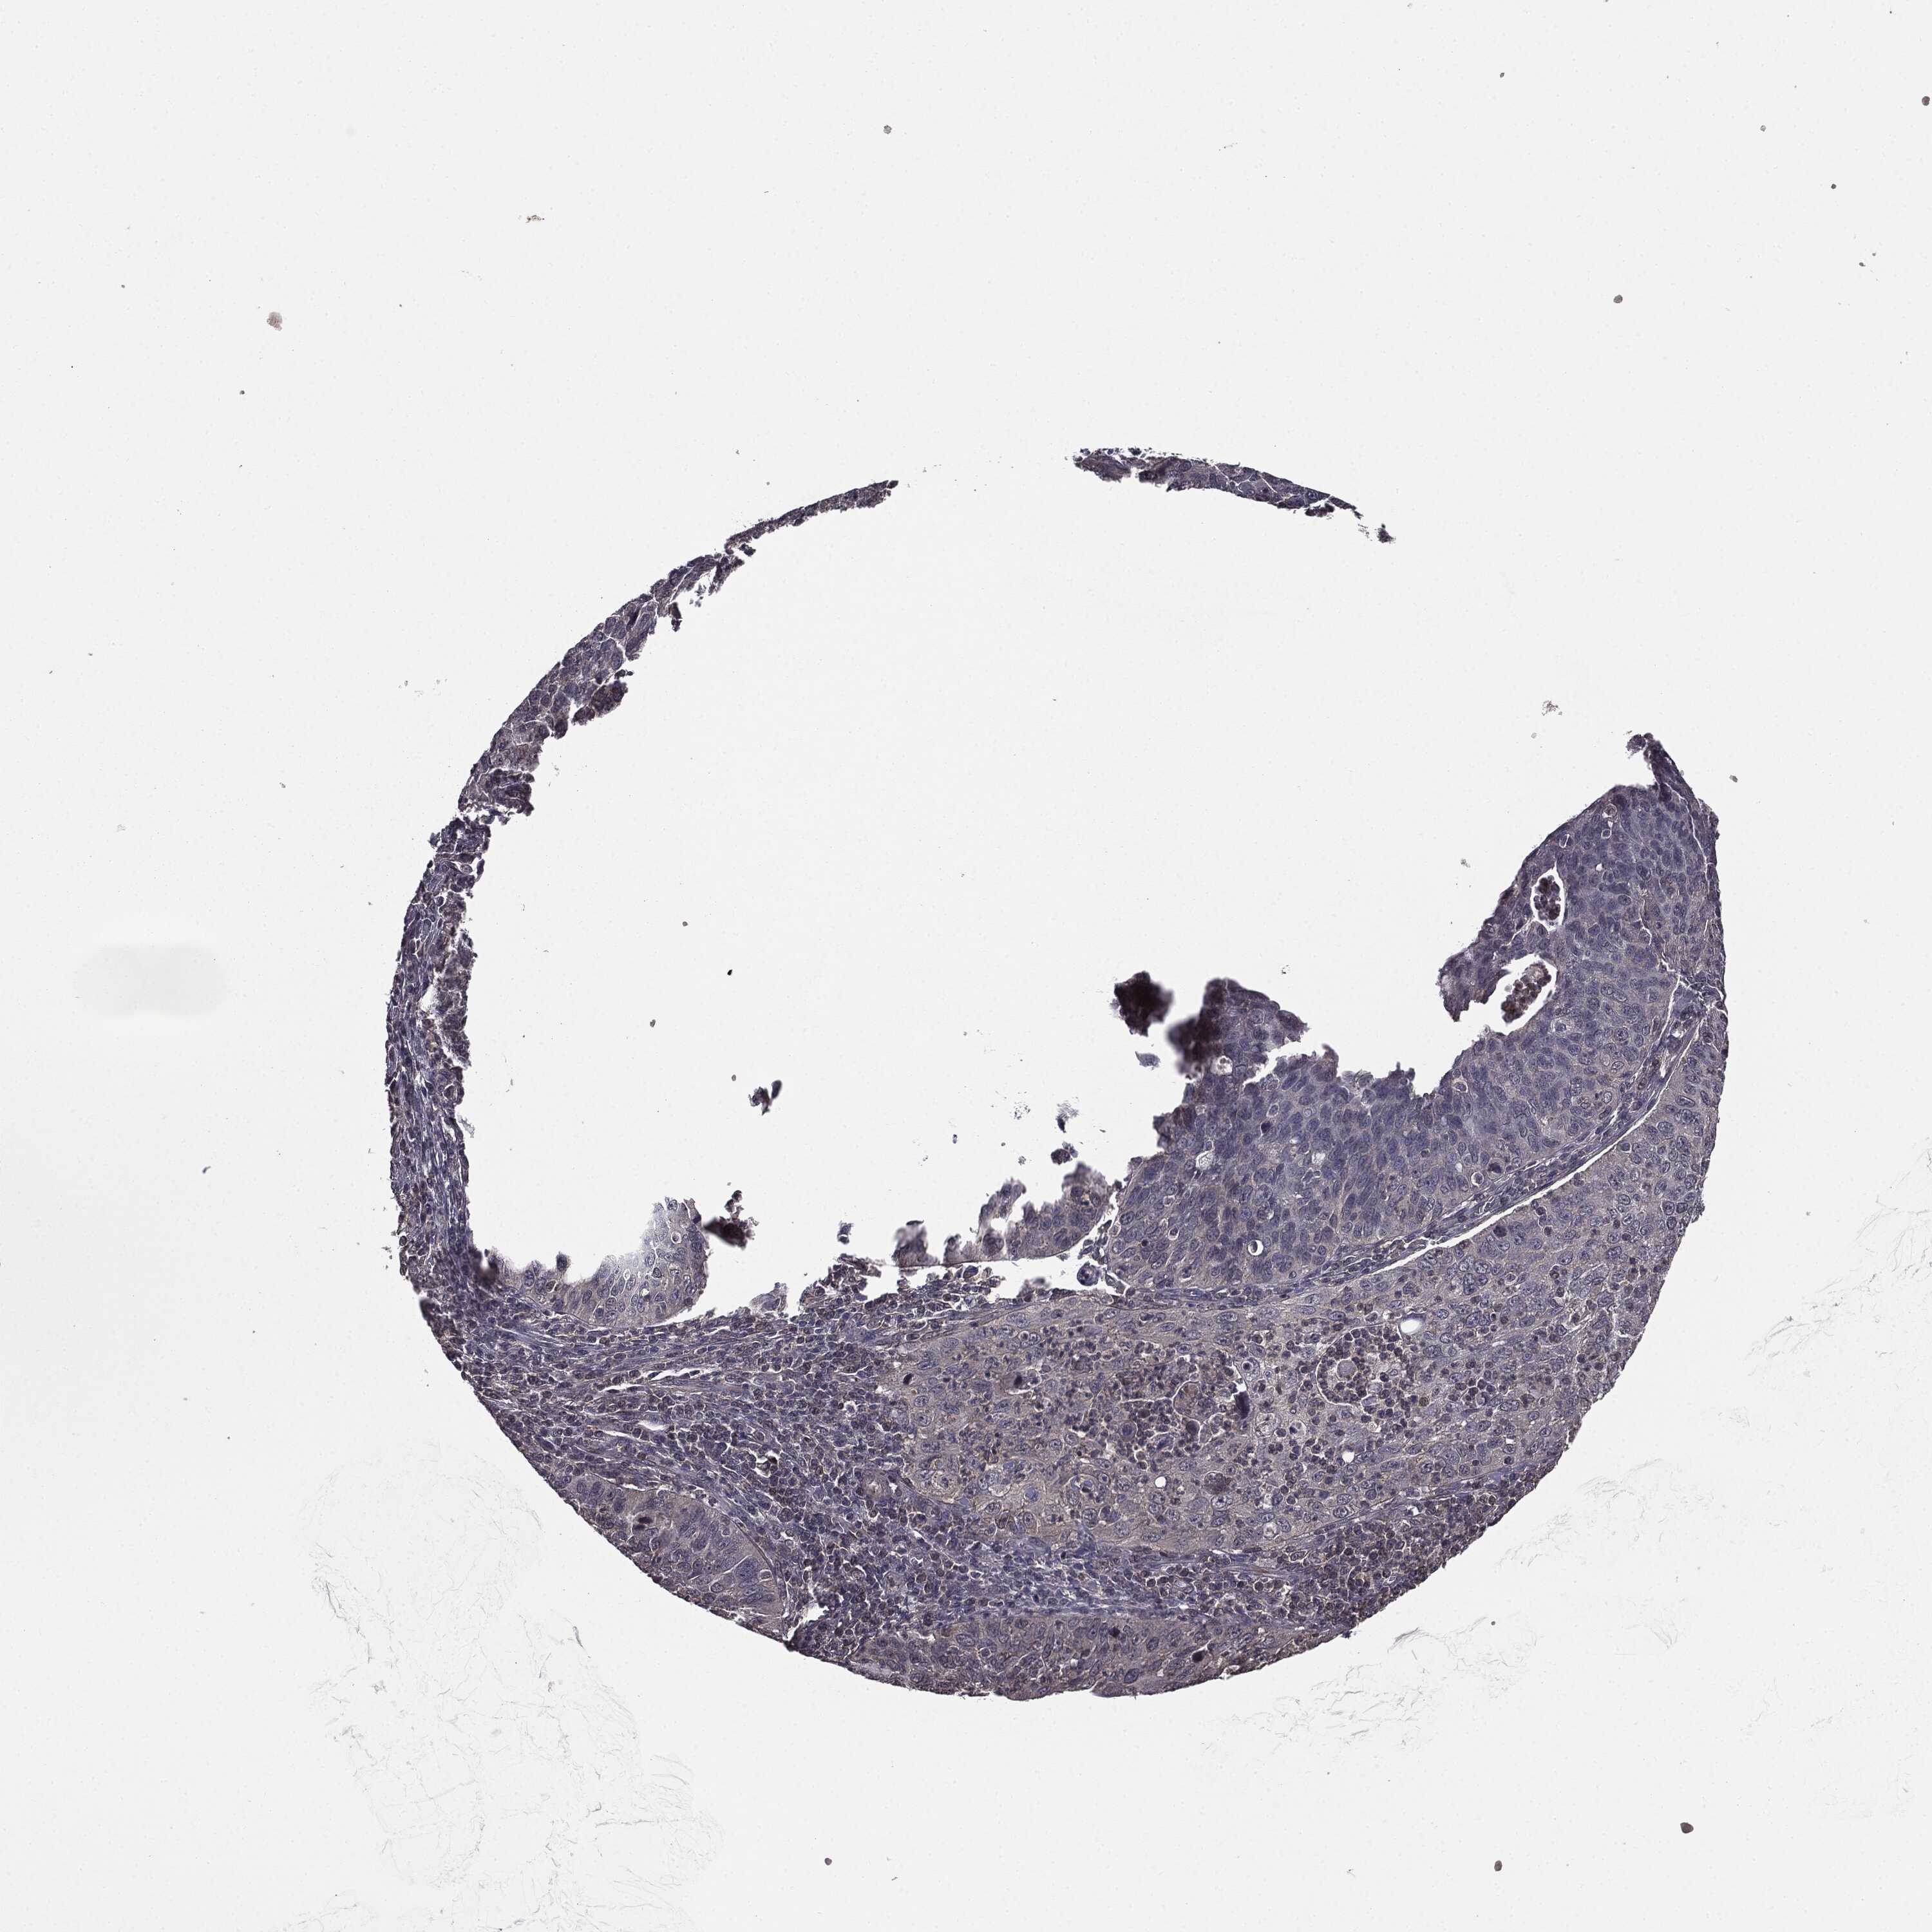

CERVICAL CANCER - Protein expressioni

A mouse-over function shows sample information and annotation data. Click on an image to view it in a full screen mode. Samples can be filtered based on level of antibody staining by selecting one or several of the following categories: high, medium, low and not detected. The assay and annotation is described here.

Note that samples used for immunohistochemistry by the Human Protein Atlas do not correspond to samples in the TCGA dataset.

Antibody stainingi

Antibody staining in the annotated cell types in the current human tissue is reported as not detected, low, medium, or high, based on conventional immunohistochemistry profiling in selected tissues. This score is based on the combination of the staining intensity and fraction of stained cells.

Each image is clickable and will lead to virtual microscopy that enables deeper exploration of all samples and also displays staining intensity scores, fraction scores and subcellular localization as well as patient and tissue information for each sample.

Antibody HPA052606

Antibody HPA077139

Staining

High

Medium

Low

Not detected

Intensity

Strong

Moderate

Weak

Negative

Quantity

>75%

75%-25%

<25%

None

Location

Nuclear

Cytoplasmic/membranous

Cytoplasmic/membranous,nuclear

Squamous cell carcinoma, NOS

Adenocarcinoma, NOS